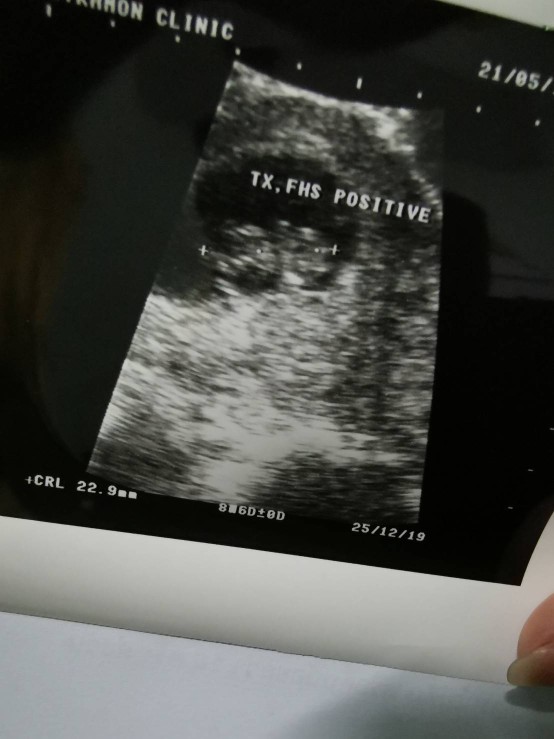

แม่ท้อง 8วีค ขนาดเท่านี้มั้ยคะ ท้องที่แล้ว 5 วีคแท้งค่ะ ขอดูแม่ท้อง 8 วีคหน่อยค่ะ ว่าเหมือนกันมั้ย กลัวไม่ปกติค่ะ ?

8W6D ค่ะ